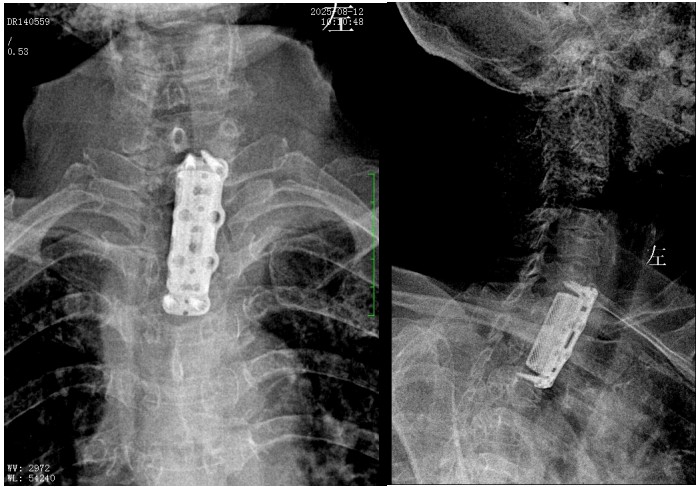

錢軍博士組織團隊進行了詳盡的術(shù)前討論,充分的術(shù)前準備后,于8月10日為患者實施了“前路病灶清除、人工椎體植入、植骨融合內(nèi)固定術(shù)”。順利完成了徹底清除病灶,椎管減壓解除脊髓壓迫,矯正后凸畸形,重建脊柱穩(wěn)定性的手術(shù)目標。